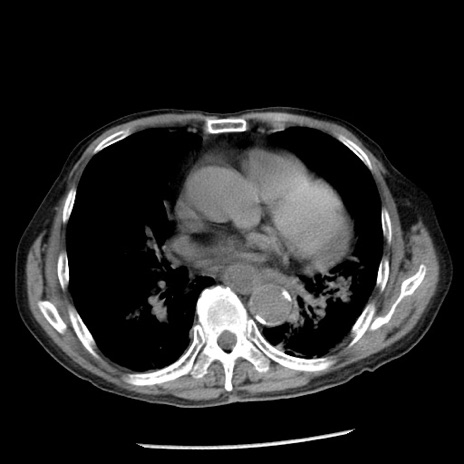

冠状断像

【症例】80歳代男性

【主訴】嘔吐

【現病歴】昨晩2回嘔吐あり、今朝になっても嘔吐あり。来院。

【既往歴】胃潰瘍

【身体所見】意識清明、BT 37.6℃、BP 166/95mmHg、HR 100bpm、SpO2 97%、腹部:平坦・軟、腸蠕動音聴取良好、圧痛なし。

【データ】WBC 21900、CRP 1.46